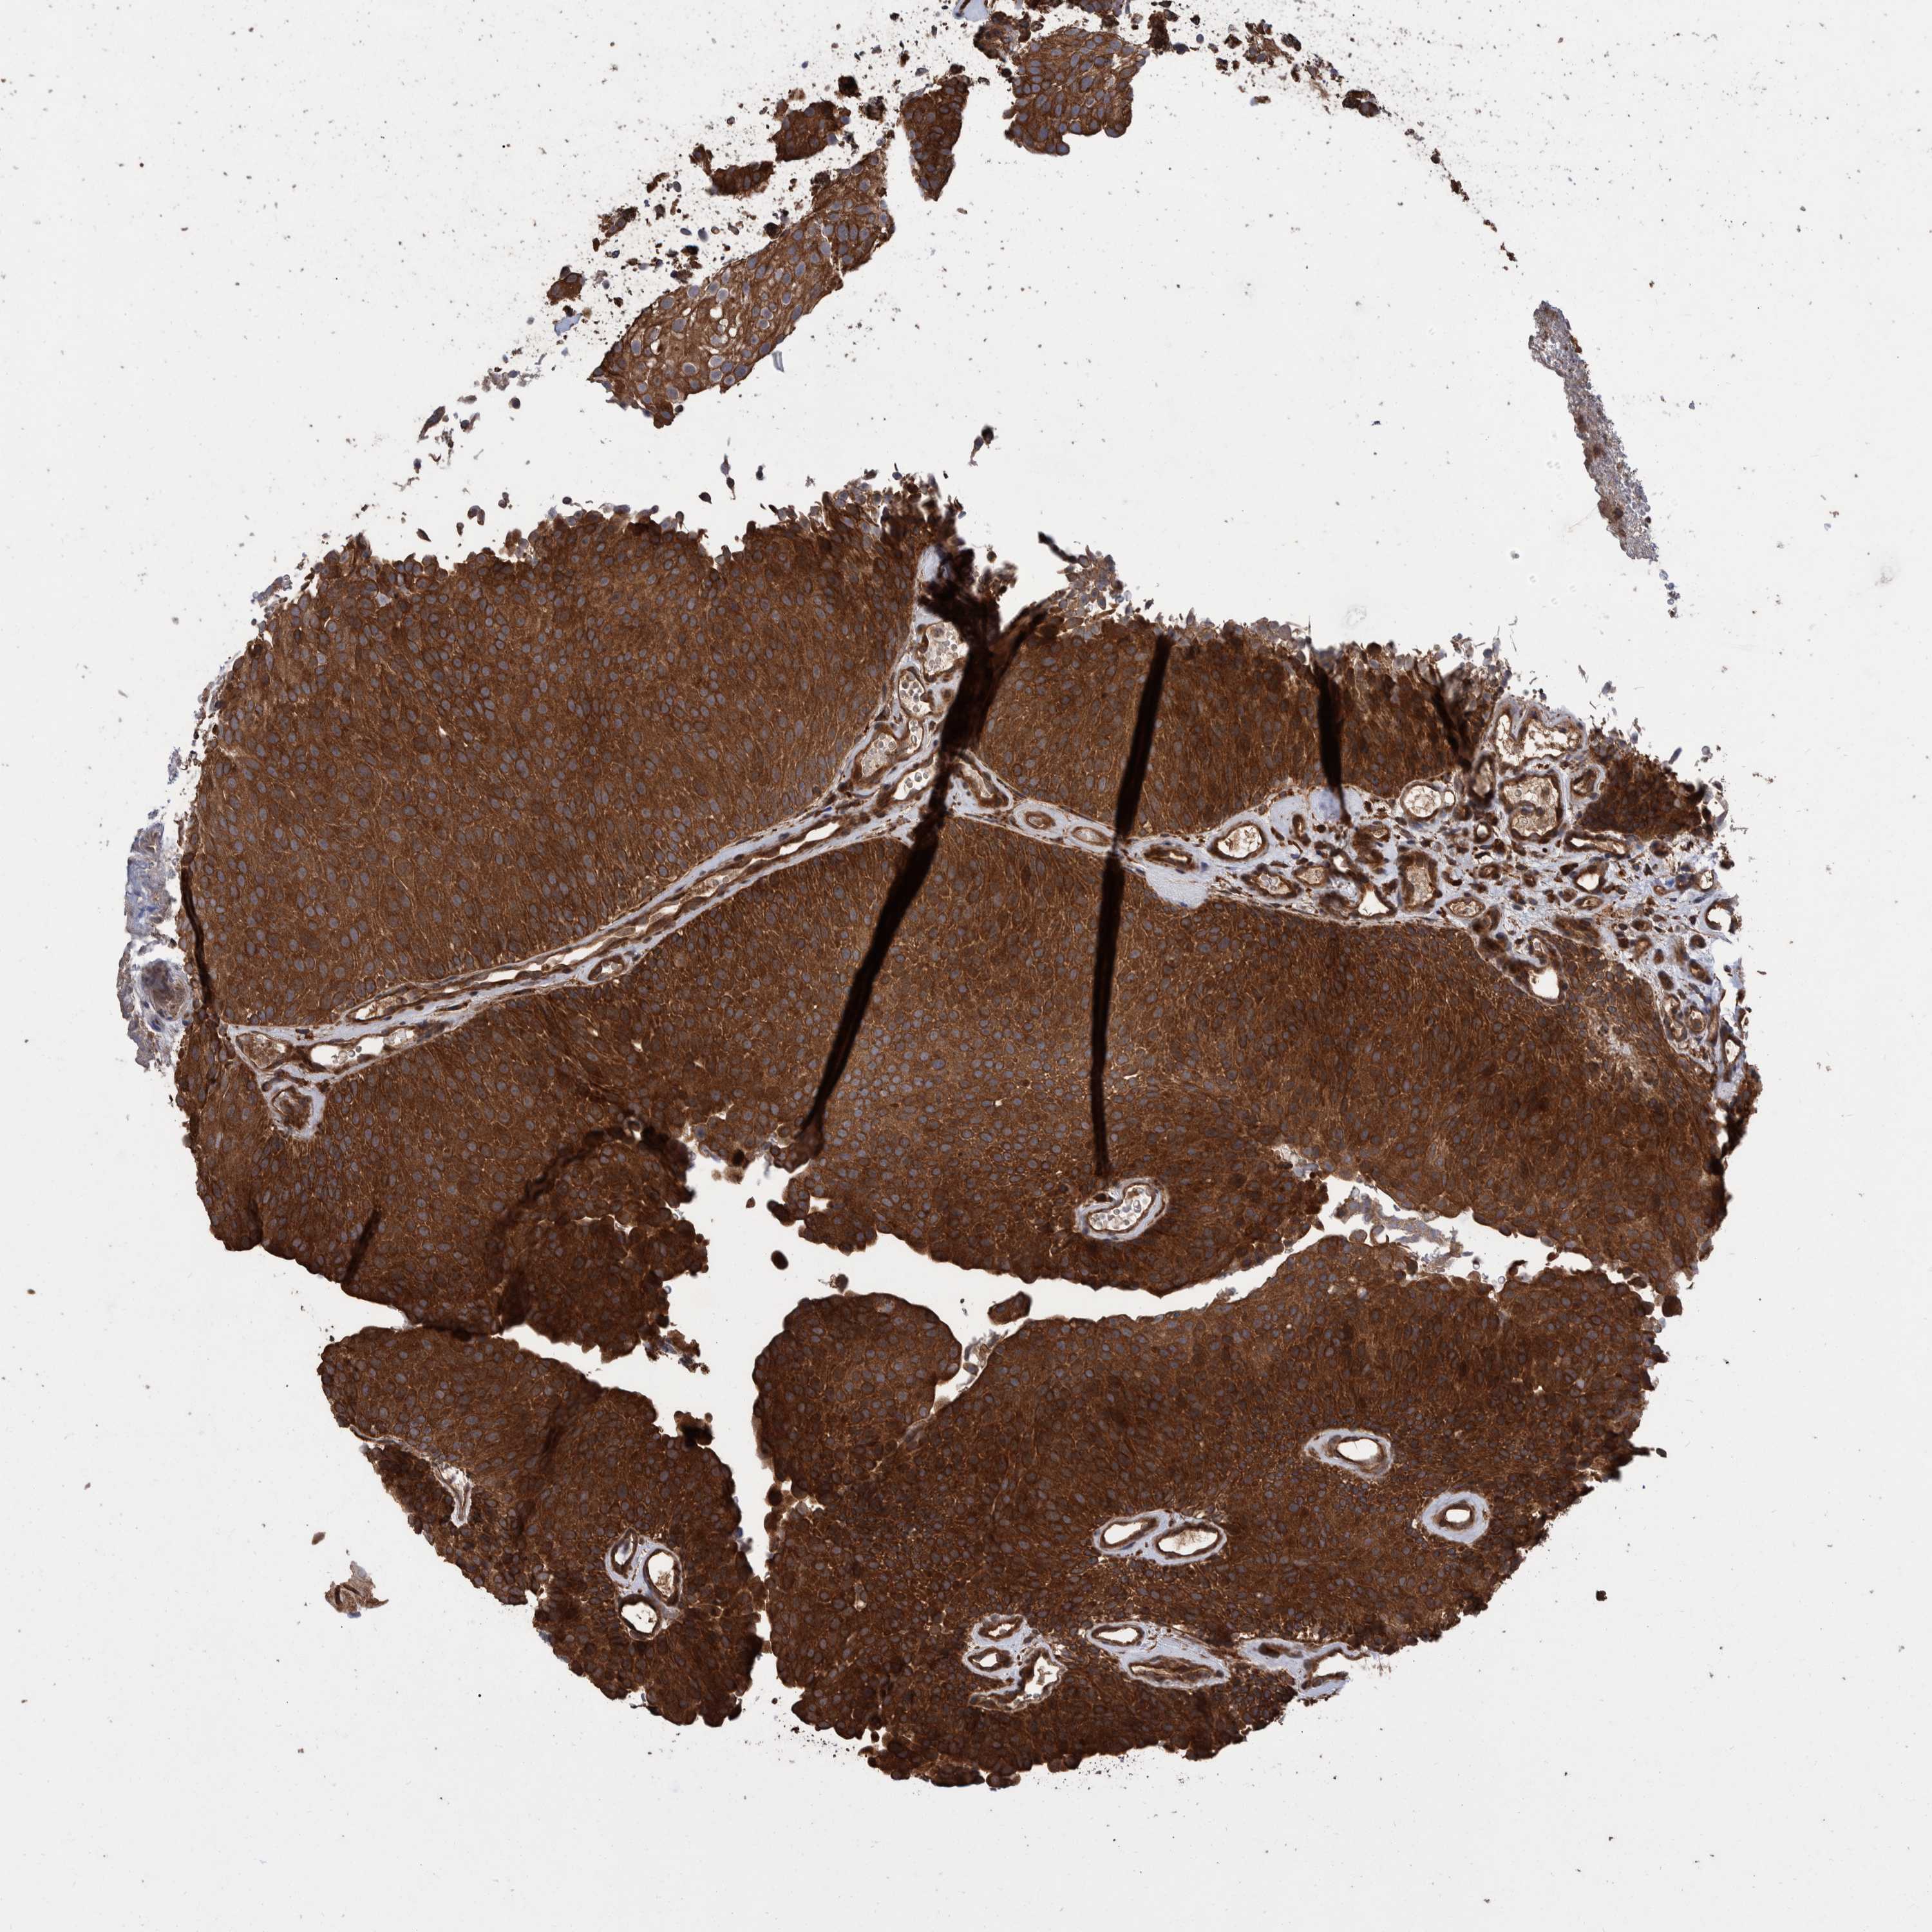

UROTHELIAL CANCER - Protein expressioni

A mouse-over function shows sample information and annotation data. Click on an image to view it in a full screen mode. Samples can be filtered based on level of antibody staining by selecting one or several of the following categories: high, medium, low and not detected. The assay and annotation is described here.

Note that samples used for immunohistochemistry by the Human Protein Atlas do not correspond to samples in the TCGA dataset.

Antibody stainingi

Antibody staining in the annotated cell types in the current human tissue is reported as not detected, low, medium, or high, based on conventional immunohistochemistry profiling in selected tissues. This score is based on the combination of the staining intensity and fraction of stained cells.

Each image is clickable and will lead to virtual microscopy that enables deeper exploration of all samples and also displays staining intensity scores, fraction scores and subcellular localization as well as patient and tissue information for each sample.

Antibody HPA023230

Antibody CAB006260

Urothelial carcinoma, Low grade

Urothelial carcinoma, High grade